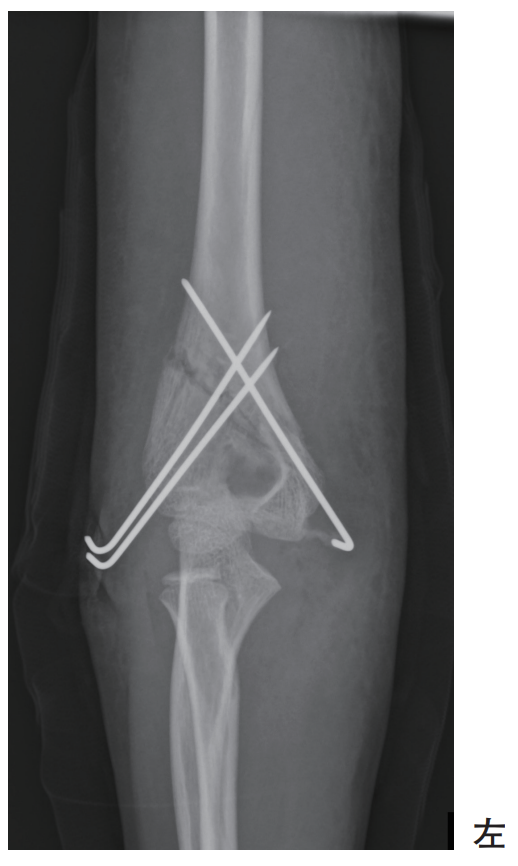

6歳の女児。公園で転倒し、骨折の診断で同日緊急手術を受けた。術後のエックス線写真を別に示す。

術後の患側上肢の理学療法で正しいのはどれか。